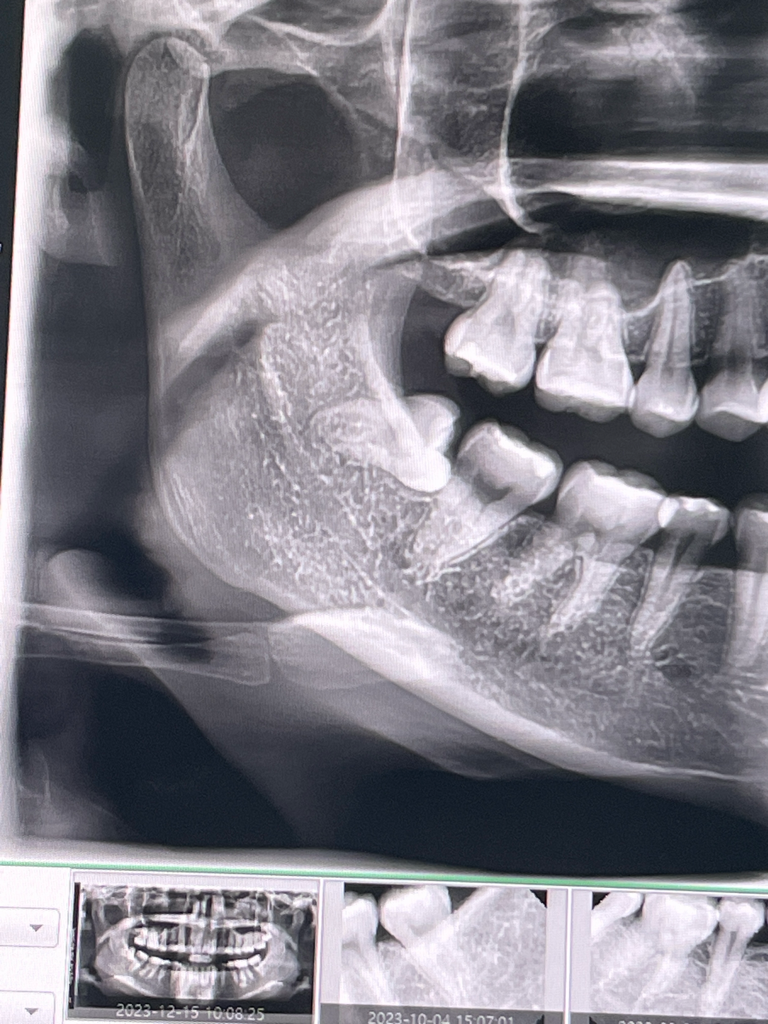

매복사랑니 발치는 11월 15일 오전 11시에 했어요

엑스레이사진대로 조금 어려운 수술이라고 하셨습니다.

• 1번 째 사진

• 2번 째 사진

• 3번 째 사진